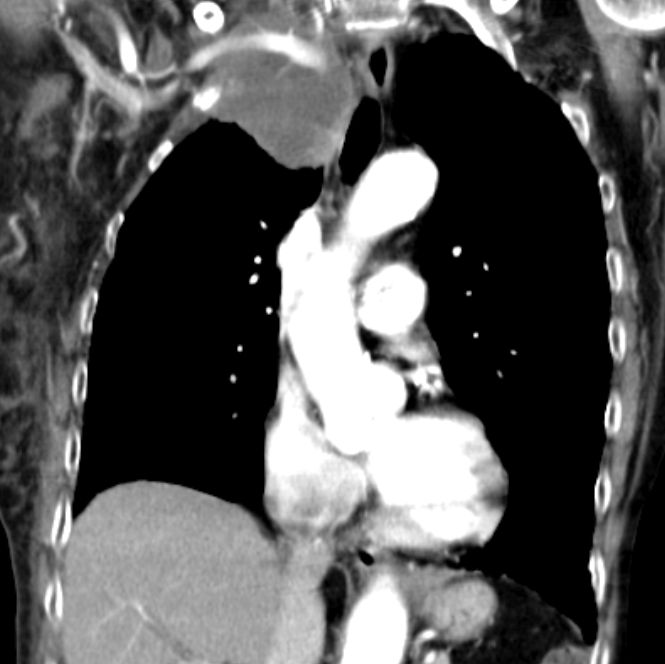

| Pancoast linker Oberlappen | 63-jähriger Mann mit einem Plattenepithelkarzinom

des linken Lungenoberlappens. Klinisch faustgroßes Vorwölbung über dem

linken Schlüsselbein.![]() |

Die Infiltrate haben die A. subclavia

eingeschlossen. Klinisch schlaffe Lähmung des linken Arm mit lividität.

Zusätzlich Verengung des Lidspaltes links.![]() | |